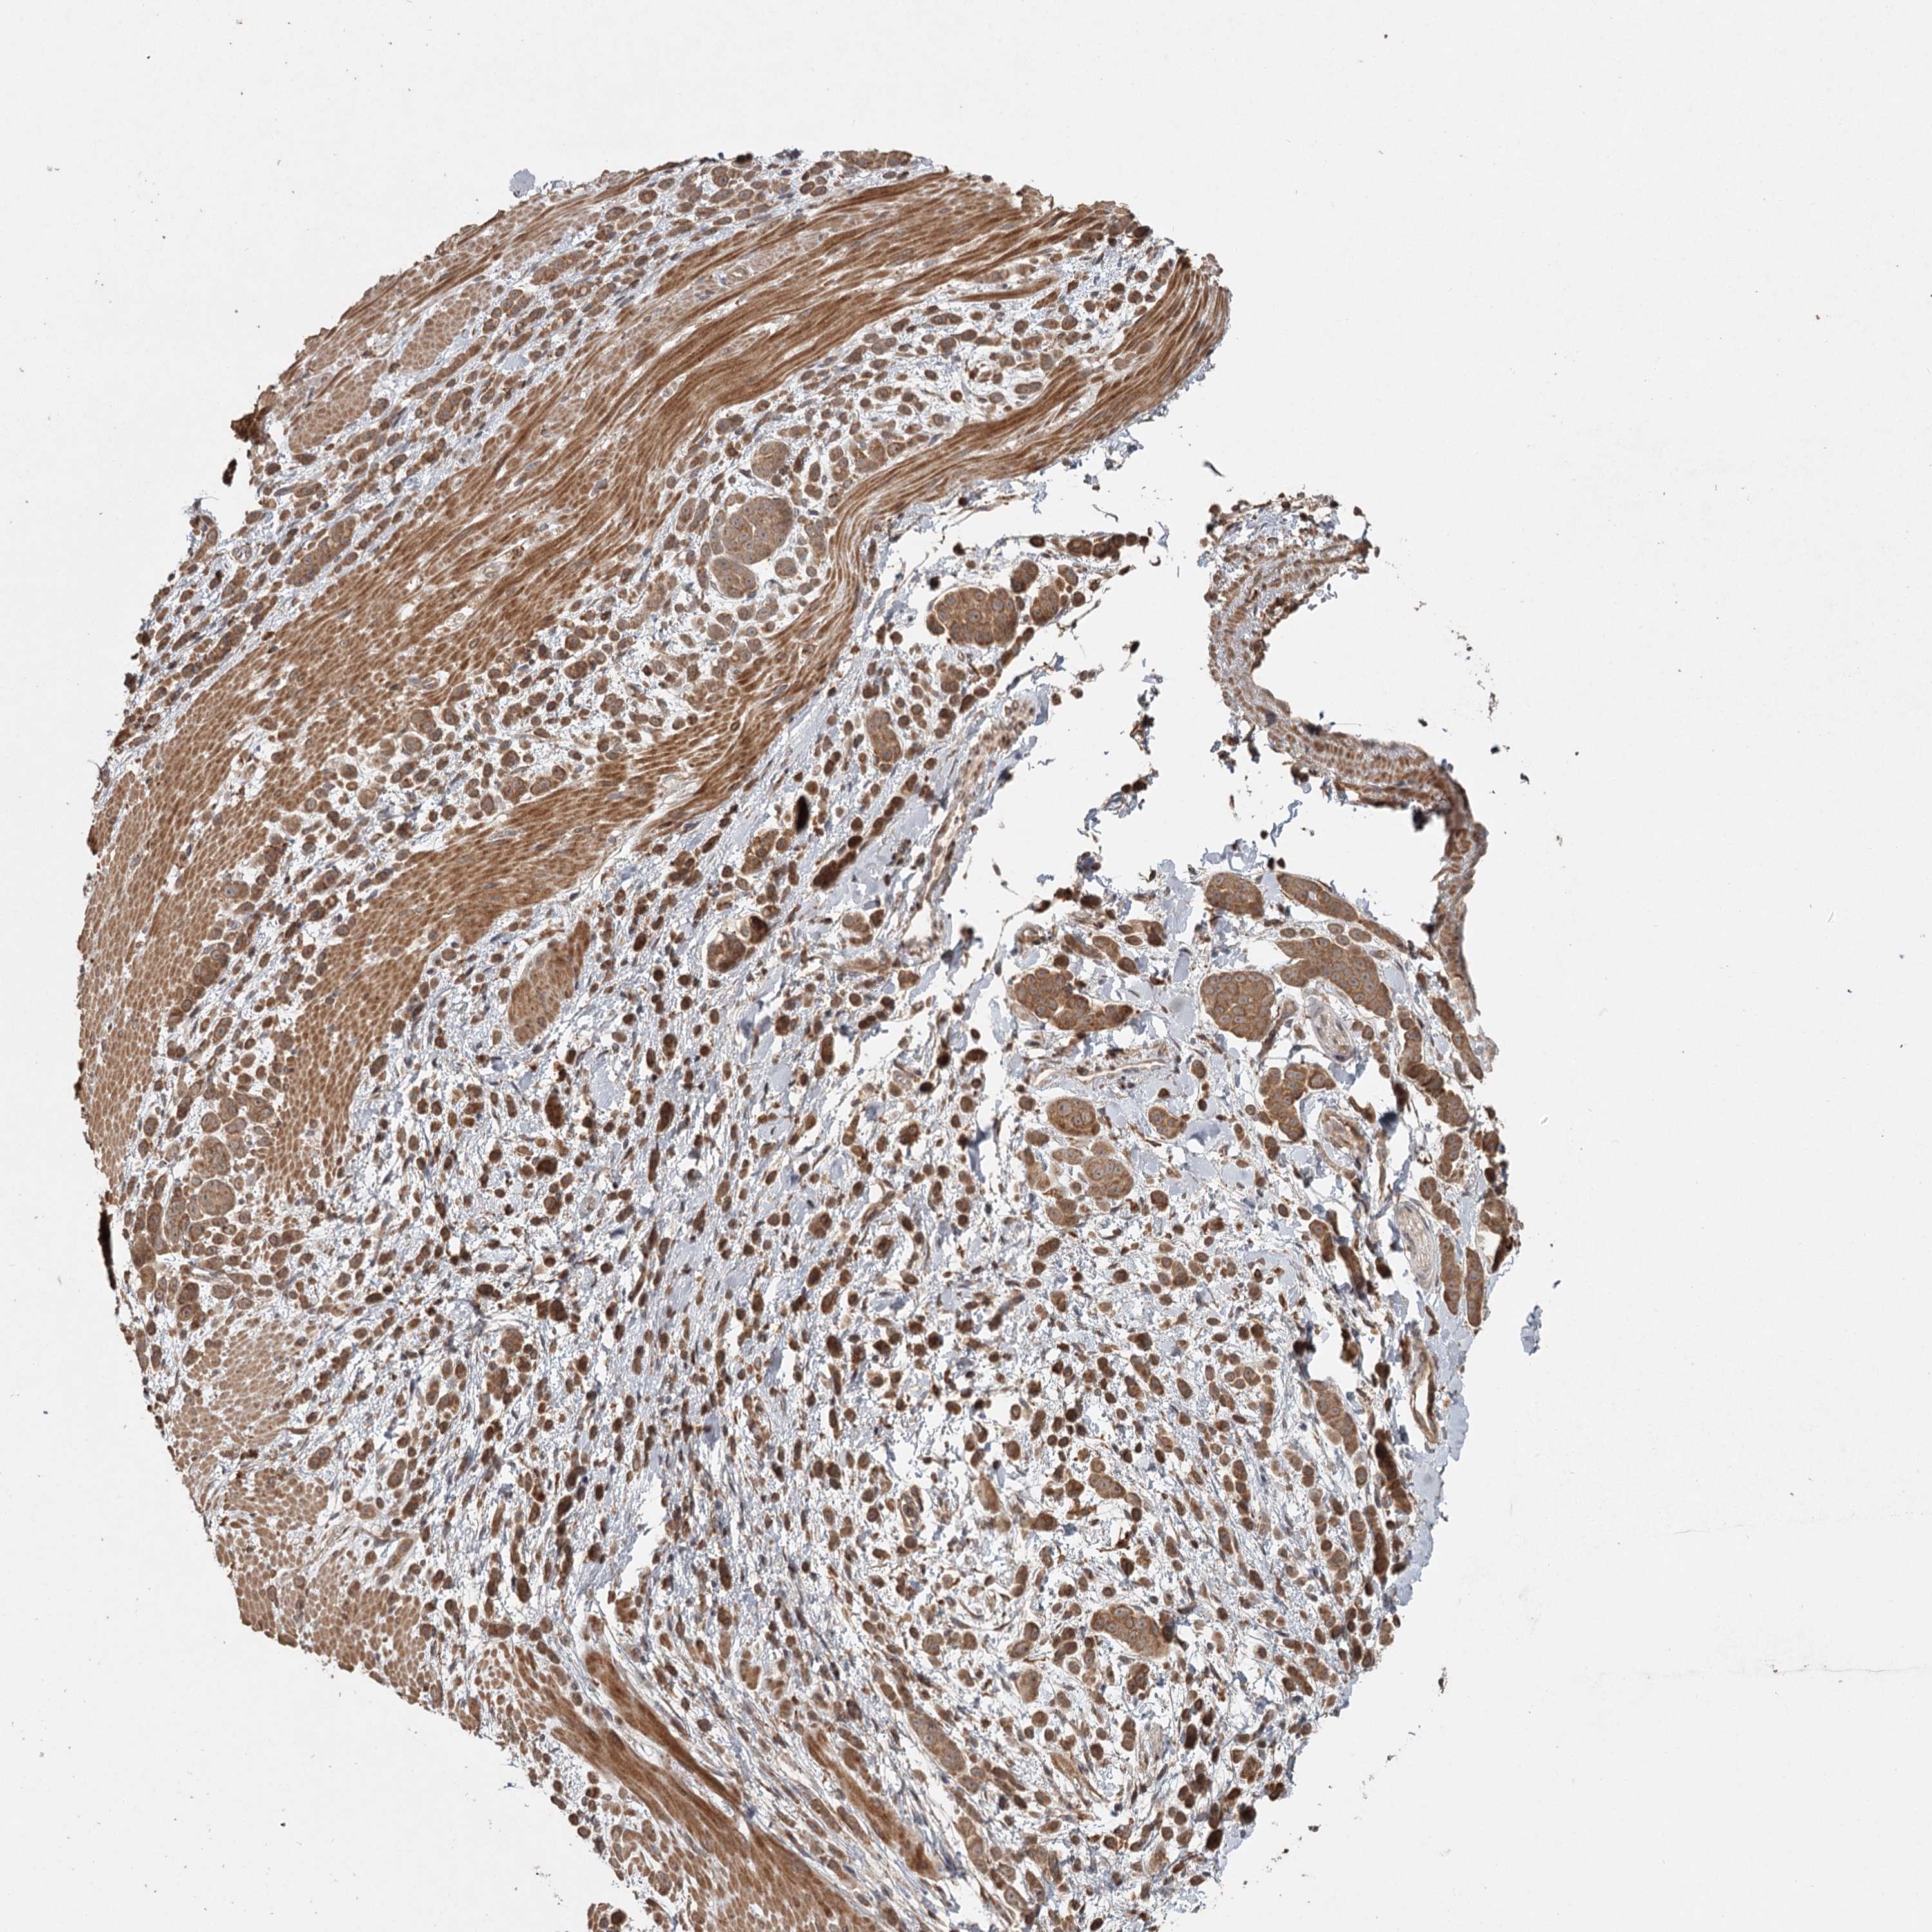

PANCREATIC CANCER - Protein expressioni

A mouse-over function shows sample information and annotation data. Click on an image to view it in a full screen mode. Samples can be filtered based on level of antibody staining by selecting one or several of the following categories: high, medium, low and not detected. The assay and annotation is described here.

Note that samples used for immunohistochemistry by the Human Protein Atlas do not correspond to samples in the TCGA dataset.

Antibody stainingi

Antibody staining in the annotated cell types in the current human tissue is reported as not detected, low, medium, or high, based on conventional immunohistochemistry profiling in selected tissues. This score is based on the combination of the staining intensity and fraction of stained cells.

Each image is clickable and will lead to virtual microscopy that enables deeper exploration of all samples and also displays staining intensity scores, fraction scores and subcellular localization as well as patient and tissue information for each sample.

Antibody HPA039106

Staining

High

Medium

Low

Not detected

Intensity

Strong

Moderate

Weak

Negative

Quantity

>75%

75%-25%

<25%

None

Location

Nuclear

Cytoplasmic/membranous

Cytoplasmic/membranous,nuclear

Adenocarcinoma, NOS